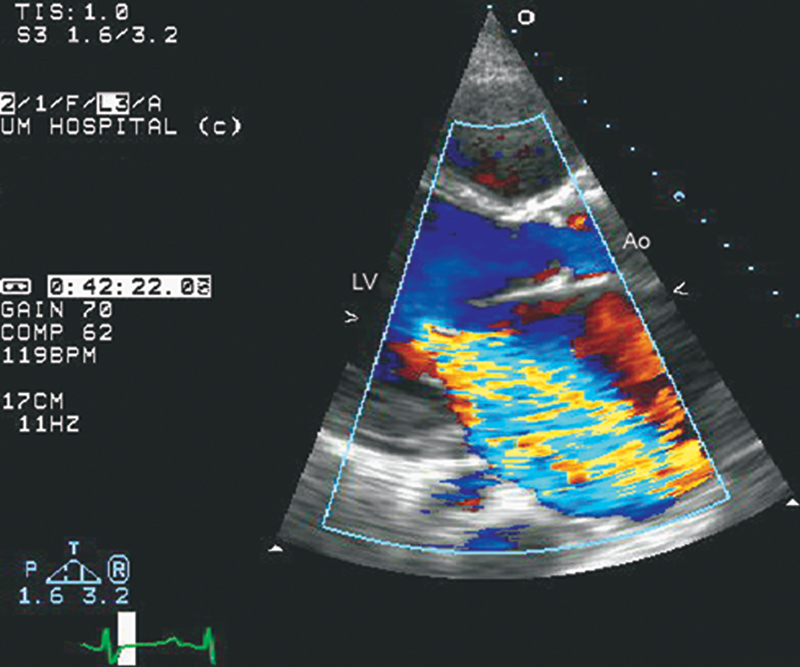

فحوصات تشخيصية لبعض امراض القلب والشرايين التاجية